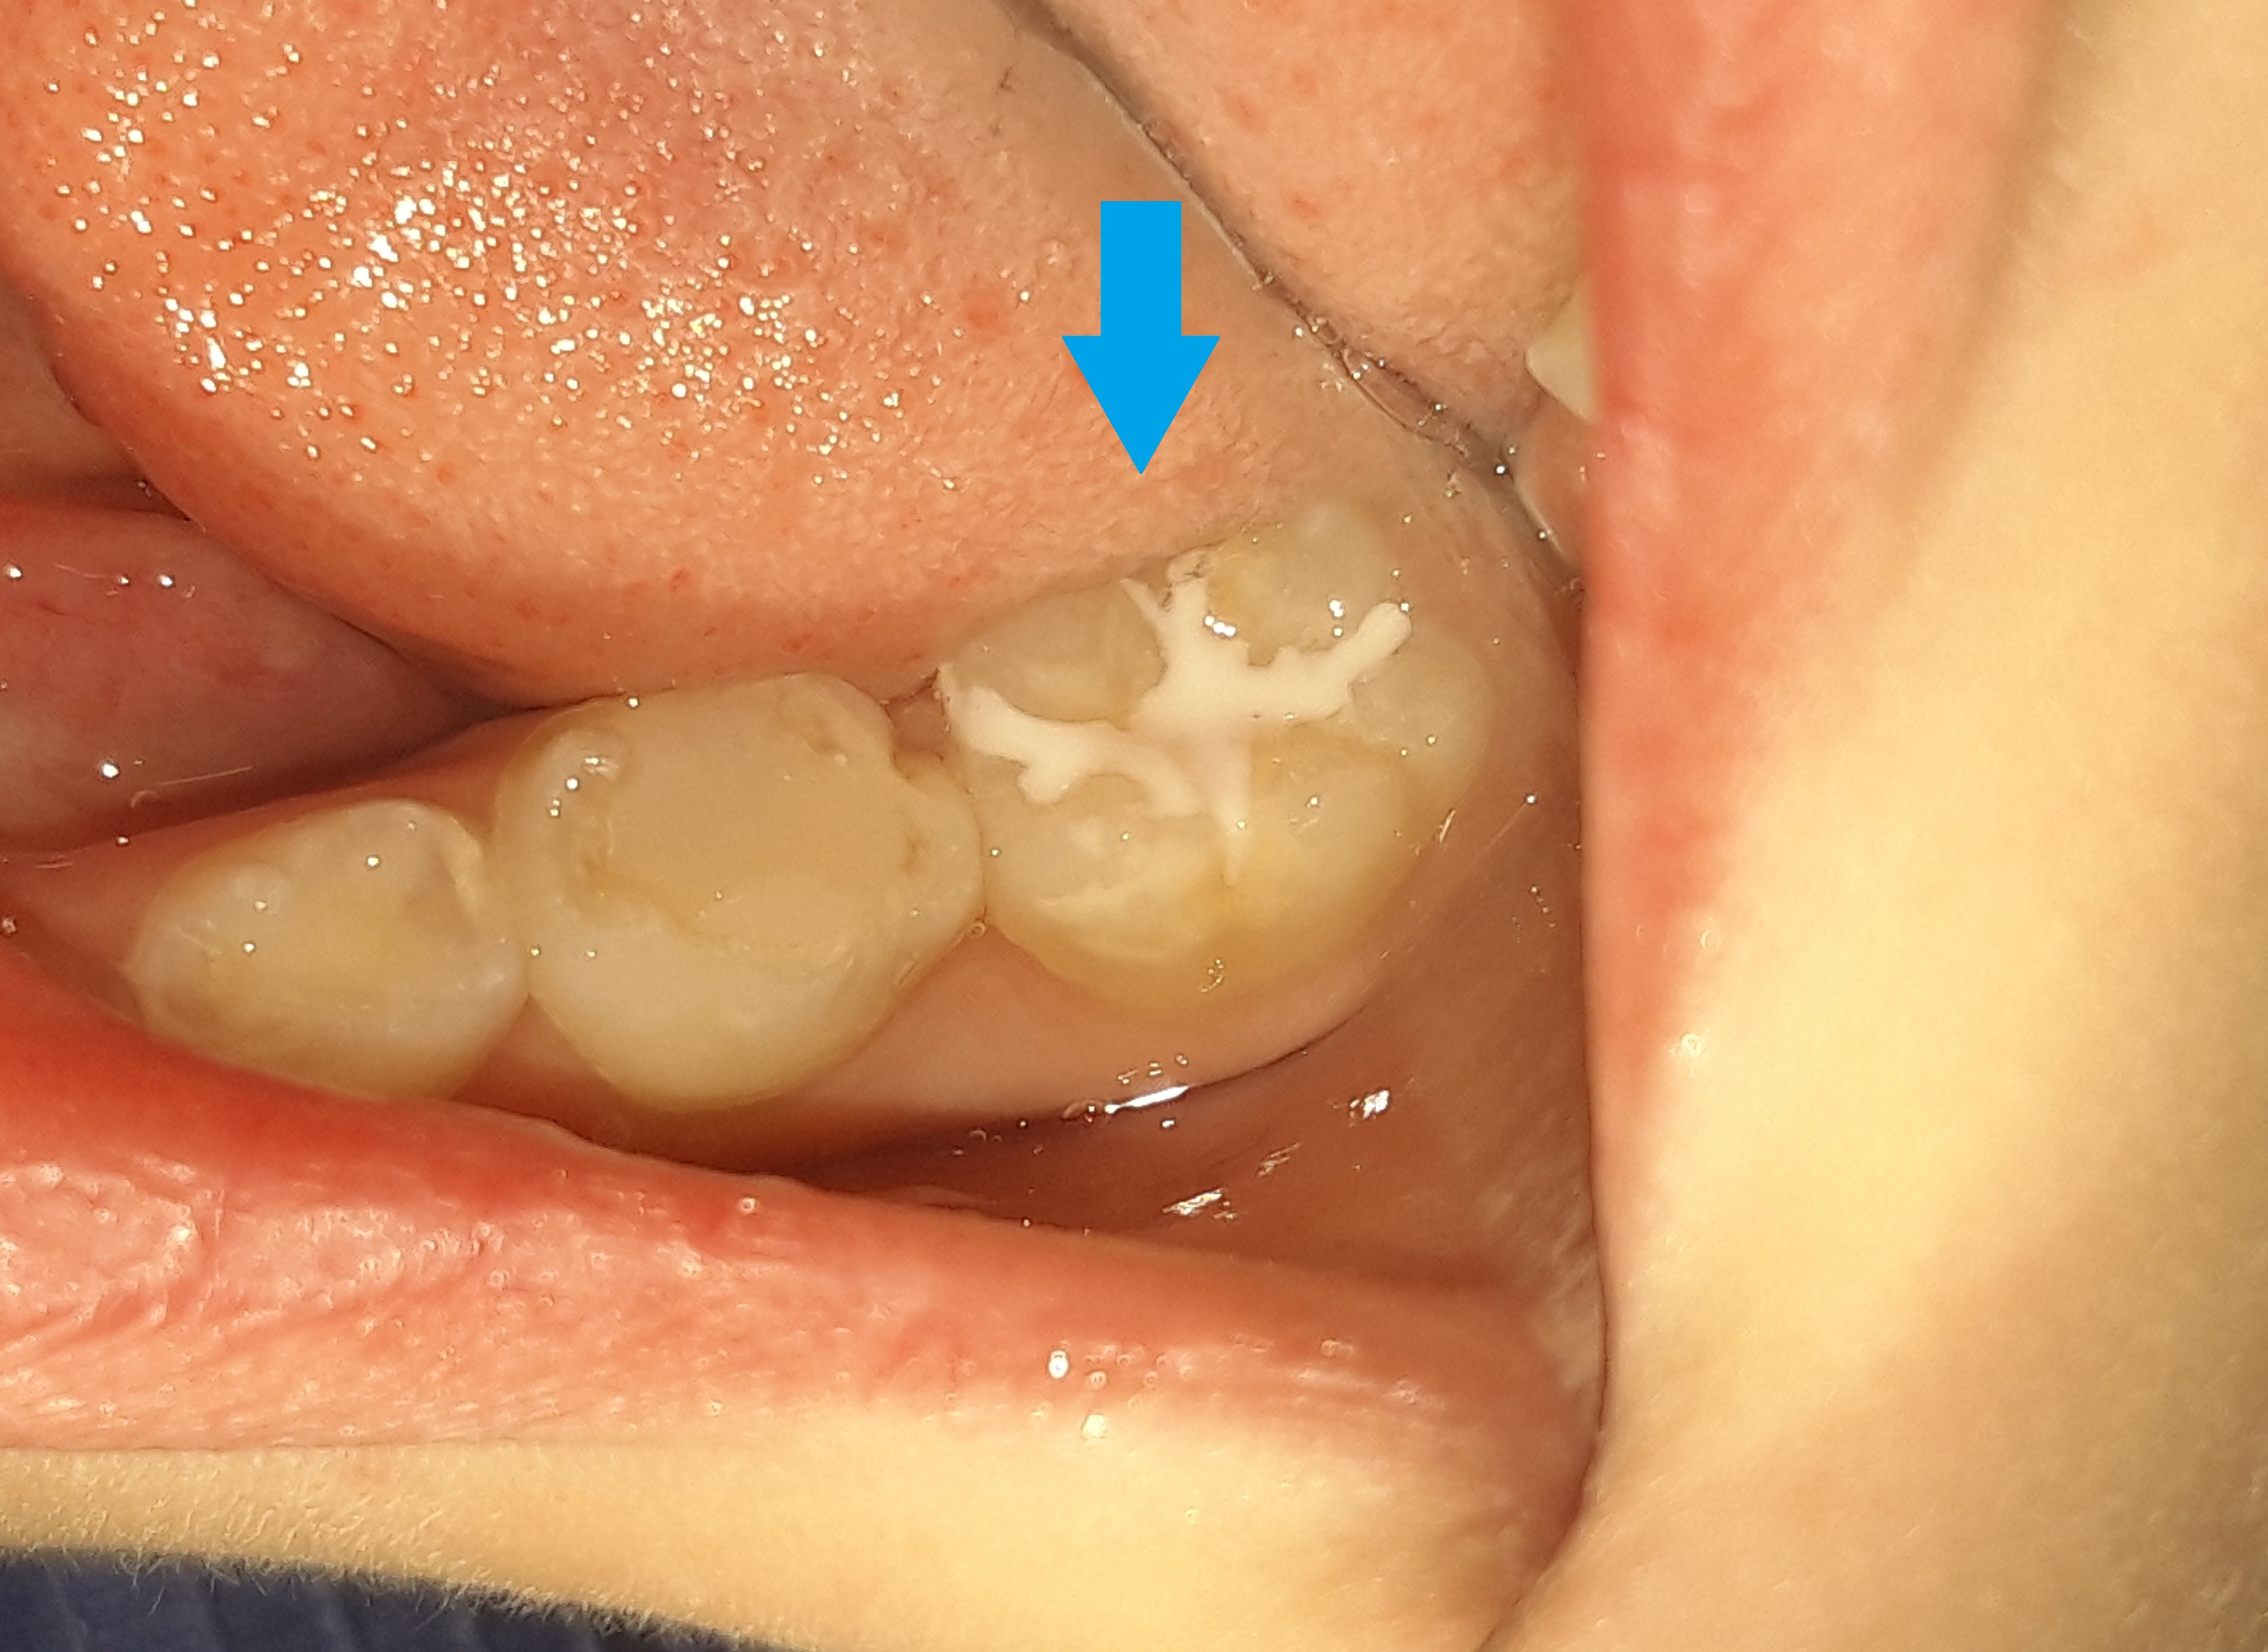

Στα πλαίσια του τυπικού οδοντιατρικού ελέγχου διαπιστώθηκε η ύπαρξη μιας μικρής τερηδονικής κοιλότητας στον πρώτο αριστερό μόνιμο γομφίο. Αποφασίστηκε η αφαίρεση της επιφανειακής αρχόμενης τερηδόνας και προληπτική κάλυψη οπών και σχισμών (sealant) στη μασητική επιφάνεια του μόνιμου άνω αριστερού πρώτου γομφίου.

Περιστατικά – Sealant / προληπτική κάλυψη οπών και σχισμών

Στο συγκεκριμένο ασθενή πραγματοποιήθηκε ταυτόχρονα αφαίρεση της επιφανειακής αρχόμενης τερηδόνας και προληπτική κάλυψη οπών και σχισμών (sealant) στη μασητική επιφάνεια του άνω αριστερού πρώτου γομφίου.